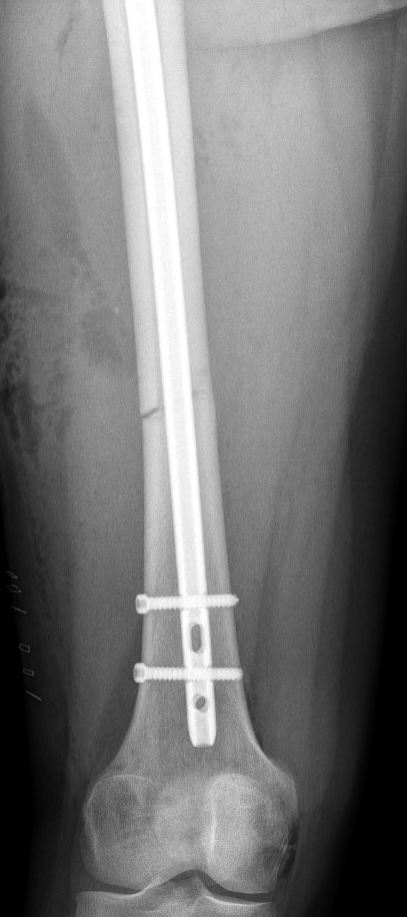

Veel gebruikt is een pen in de mergholte van het bot, die via de heup of via de knie kan worden ingebracht. De pen wordt vervolgens met dwarse schroefjes aan het begin en het einde van de pen vastgezet. Een andere optie is het gebruik van platen en schroeven om de verschillende breukdelen stevig aan elkaar vast te zetten. Voor het plaatsen van een plaat is wel een grotere snede nodig dan voor een pen. Indien er sprake is van een ernstig weke delen letsel en zeker als er meerdere ernstige letsels tegelijk aanwezig zijn, kan uw chirurg er ook voor kiezen om de breuk, al dan niet tijdelijk, van buitenaf vast te zetten met een extern fixatie mechanisme (de zogenaamde ‘externe fixateur’).